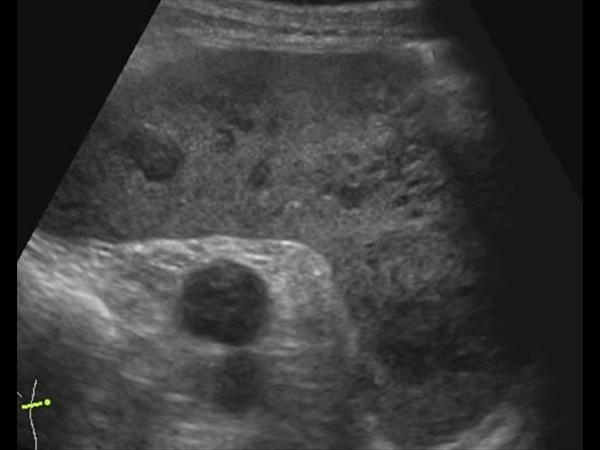

УЗИ лимфоузлов при лимфоме Ходжкина

Раздел: Образы вокруг